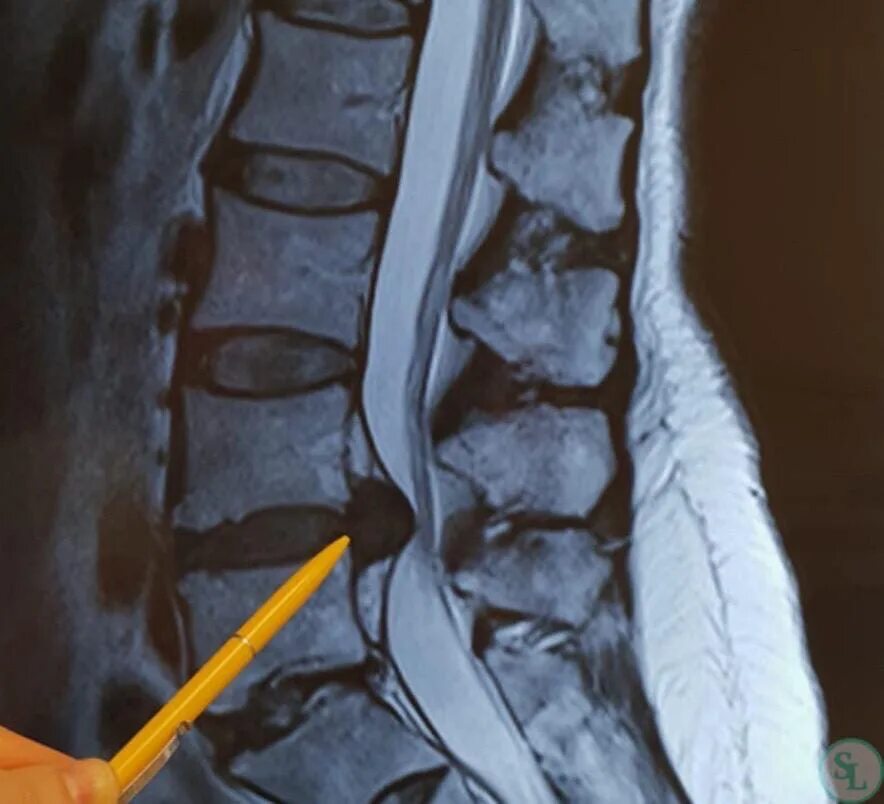

Из за чего грыжа на спине